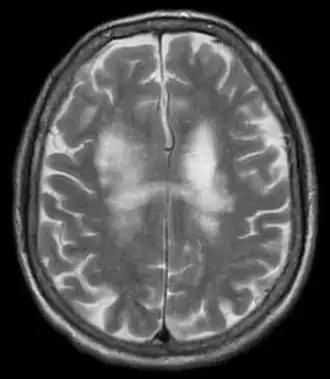

Description de l'image Progressive multifocal leukoencephalopathy 002.jpg.

Le diagnostic est évoqué devant l'apparition, chez un sujet immunodéprimé, des symptômes précédents et de lésions évocatrices sur l'IRM cérébrale (hypersignaux T2 dans la substance blanche, non rehaussés par le produit de contraste). La détection du virus JC par PCR dans le liquide cérébrospinal constitue le meilleur argument en faveur du diagnostic. Sa négativité peut faire envisager le recours à la biopsie cérébrale en cas de doute.